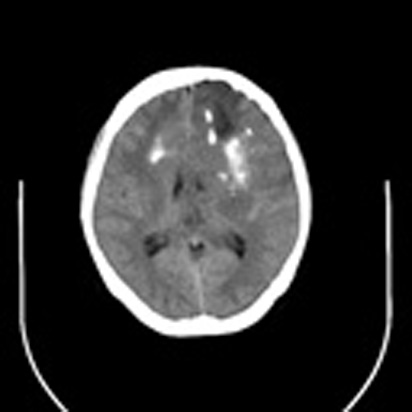

标题: CT16829:女,36,近20天偶有口眼歪斜短暂发作史,近日头痛。 [打印本页]

标题: CT16829:女,36,近20天偶有口眼歪斜短暂发作史,近日头痛。

近20天偶有口眼歪斜短暂发作史,近日头痛。患者先做ct发现病变后又做了mri检查,前日上传2次ct图像均未成功,今日补上。

少支胶质细胞瘤,胼胝体受累

大脑中线部位肿瘤向两侧生长,可见明显钙化影,考虑少枝胶质瘤,建议增强除外脑膜瘤

左额混杂密度肿块,经胼胝体跨越中线向右额叶生长,多考虑少支胶质细胞瘤,建议mr增强扫描,待排除血管畸形。

3-4级星形细胞瘤,对侧及胼胝体受侵